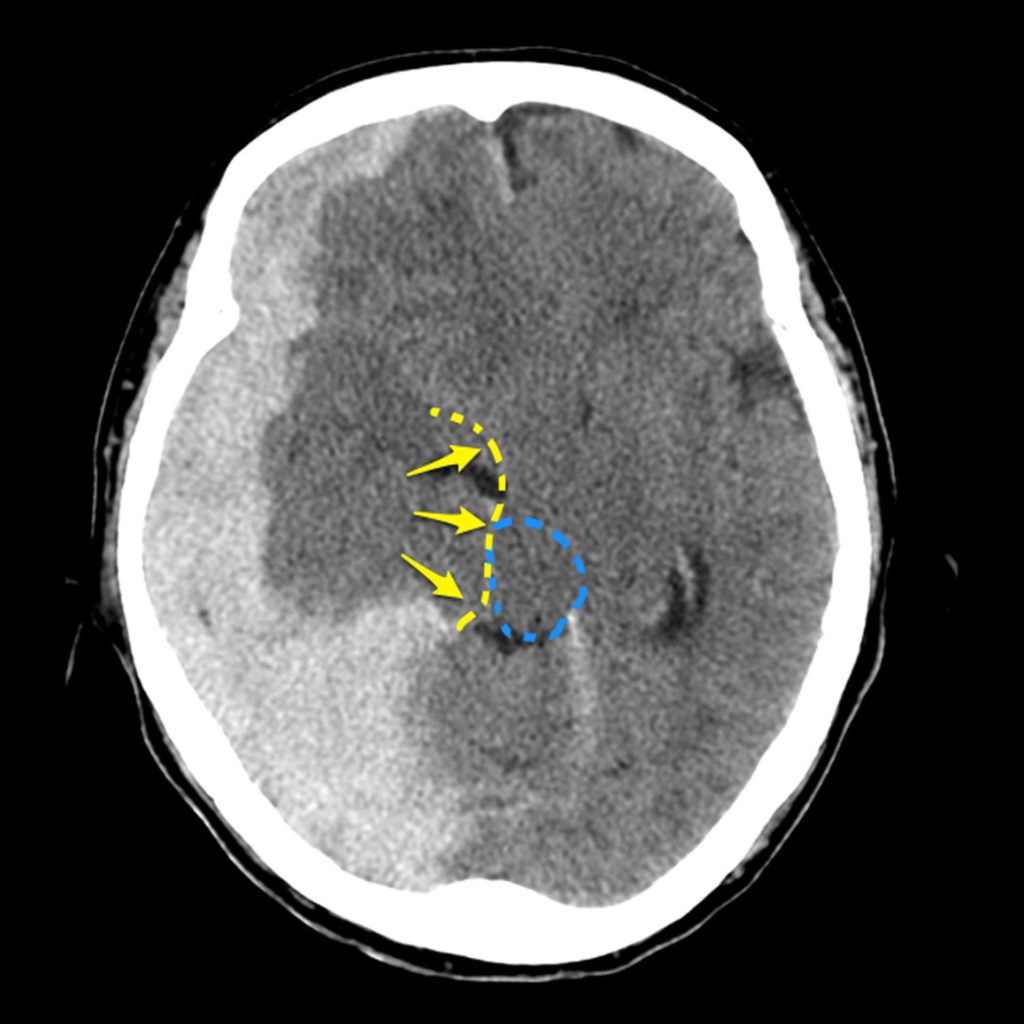

What Is A Midline Shift Of The Brain . That’s essentially what happens during a midline shift. Especially for operating on a mass or lesion or evacuating brain hematoma. It may occur following traumatic brain injury in association with raised. Midline shift describes the situation where the midline of the intracranial anatomy is no longer in the midline and is the result of pushing or pulling forces within. Often described as a midline shift, this is the most common type of brain herniation. Midline shift refers to a shift (displacement) of brain tissue across the centre line of the brain. This type of brain herniation can be further broken down into two. A midline shift of 5 mm or more is significant and is an indication for surgery; But what exactly is this midline, and why is it so crucial to our brain’s.

Midline shift refers to a shift (displacement) of brain tissue across the centre line of the brain. A midline shift of 5 mm or more is significant and is an indication for surgery; But what exactly is this midline, and why is it so crucial to our brain’s. Often described as a midline shift, this is the most common type of brain herniation. This type of brain herniation can be further broken down into two. Midline shift describes the situation where the midline of the intracranial anatomy is no longer in the midline and is the result of pushing or pulling forces within. Especially for operating on a mass or lesion or evacuating brain hematoma. It may occur following traumatic brain injury in association with raised. That’s essentially what happens during a midline shift.